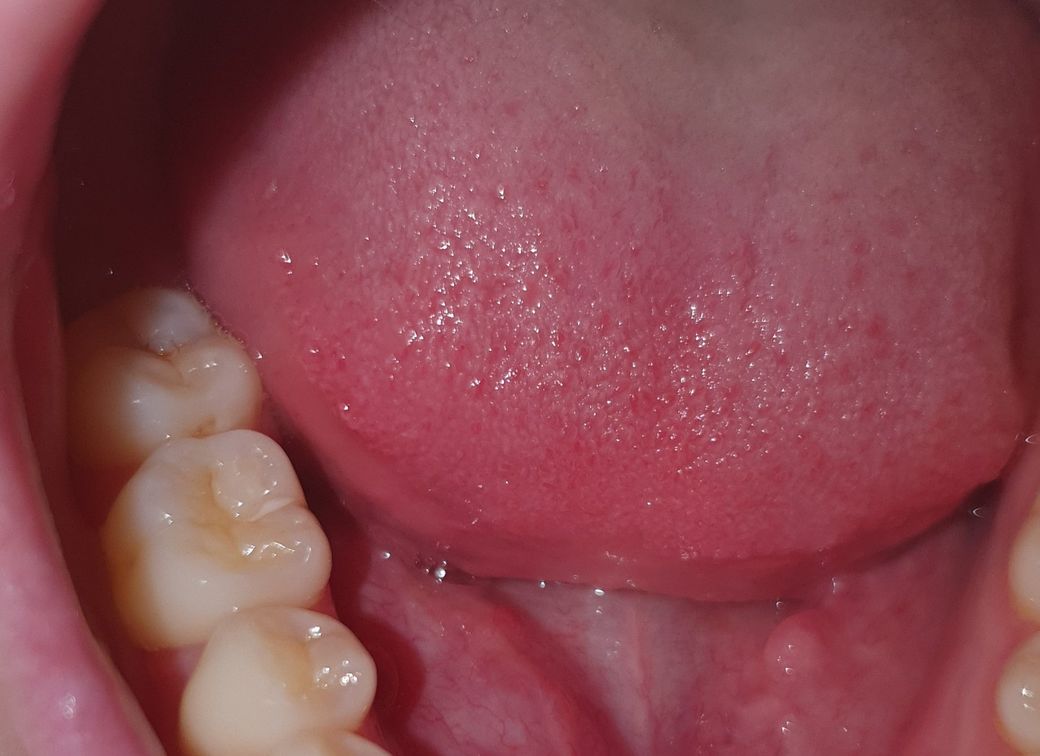

인접면충치인가요?어금니 사이에 검은점이 생겼어요

안녕하세요 어금니 사이에 좀 시꺼먼?게 생겼는데

제가 오늘 인접면충치라는걸 알게되었어요

이빨을 왕창 갈아야된다고 들었는데 혹시 이거 인접면충치인가요..?맞다면 바로 병원을가야되서 치료를 해야되는건지 집에서도 낫을수있게하거나 없애는 방법은 없을까요

• 1번 째 사진

올려주신 사진만 봤을 때는 법랑질에 국한된 충치일 수 도 있습니다.

지금 사진으로 보이는게 다이고 치아사이쪽 안보이는 곳에 충치가 없다면 굳이 당장 치료가 필요하진 않아보입니다.

하지만 치아사이 안보이는 곳에 충치가 있다면 치료가 필요할 수 도 있습니다.

충치는 잘 관리한다고 해서 없어지진 않습니다. 단, 법랑질에 국한된 충치는 관리만 잘되면 그이상 진행하지 않고 멈출 수 도 있습니다.

정확한 진단을 위해선 방사선사진과 직접 눈으로 자세히 보는 진단(시진)이 필요합니다.

따라서, 정확한 진단을 위해선 주위 치과로 내원해보시는걸 추천드립니다.